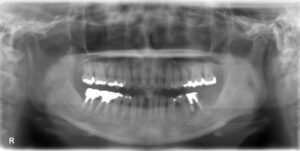

下顎大臼歯1本欠損症例

BEFORE AFTER 51歳女性/下顎1本欠損/インプラント埋込手術 【治療内容】 他院にて左下第一大臼歯の治療を受…